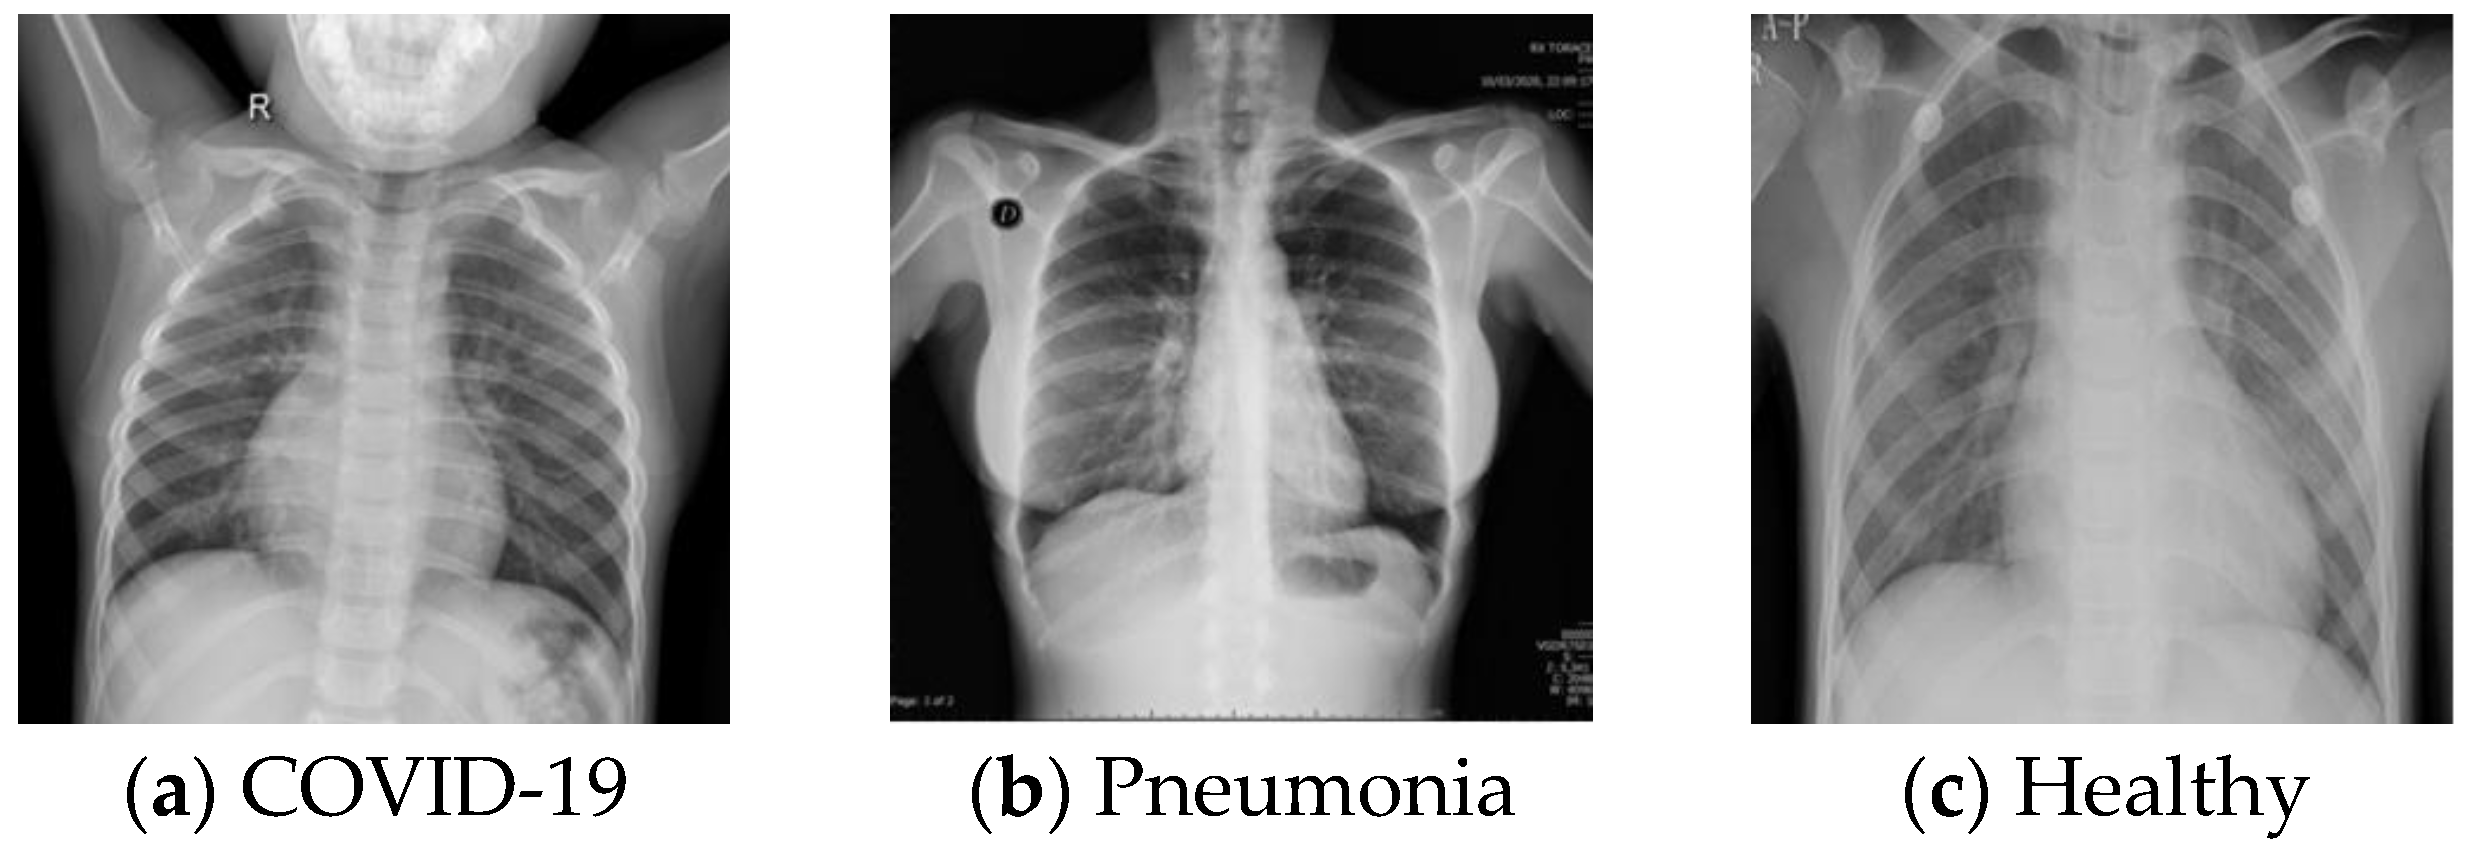

2.1.1. The First Database (DB1)

2.1.2. The Second Database (DB2)

2.1.3. The Third Database (DB3)

2.1.4. The Fourth Database (DB4)